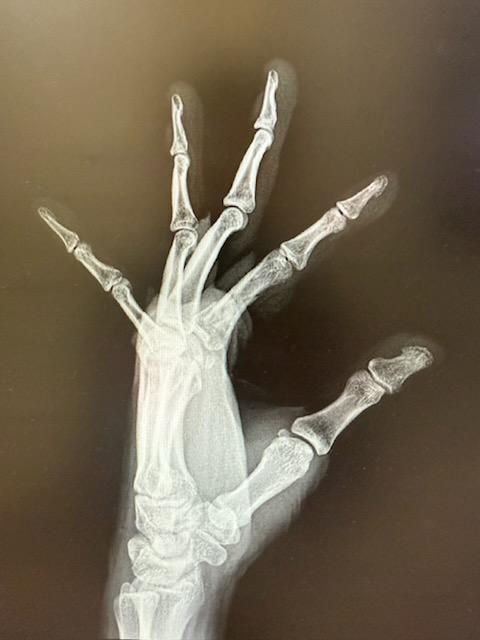

5월7일 검지손가락 핀고정수술 후 6월9일 뼈가 붙지않았지만 재활차 핀제거를 하였습니다. 그로부터 2주 후 6월24일자 x-ray사진입니다. 뼈가 잘 붙을까요?

수술 후 7주차인 지금 엑스레이에서 골절 부위에 윤관기 흐려지고 연결선이 옅어졌다면 뼈가 붙는 중일 가능성이 높습니다

특히 핀 제거 후에도 골간단 부위에 뼈 생성 소견이 보이면 회복 방향으로 가고 있는 겁니다.

다만 손가락은 움직임이 많아 미세한 불안정성이나 지연 유합 가능성도 있으므로 지속적 재활과 정기 엑스레이 추적이 중요합니다!